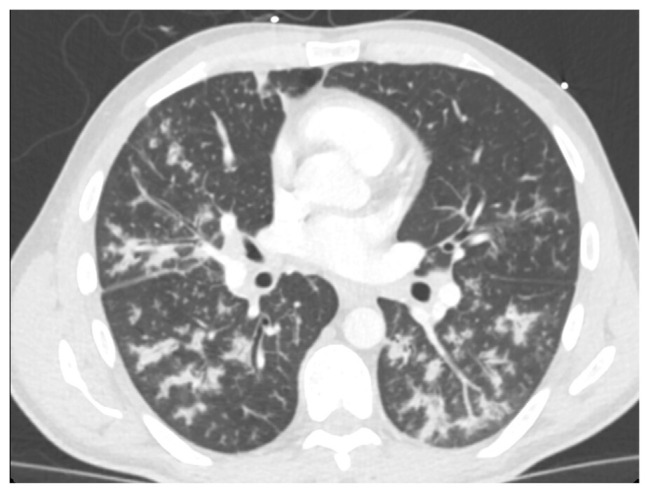

Abstract Image